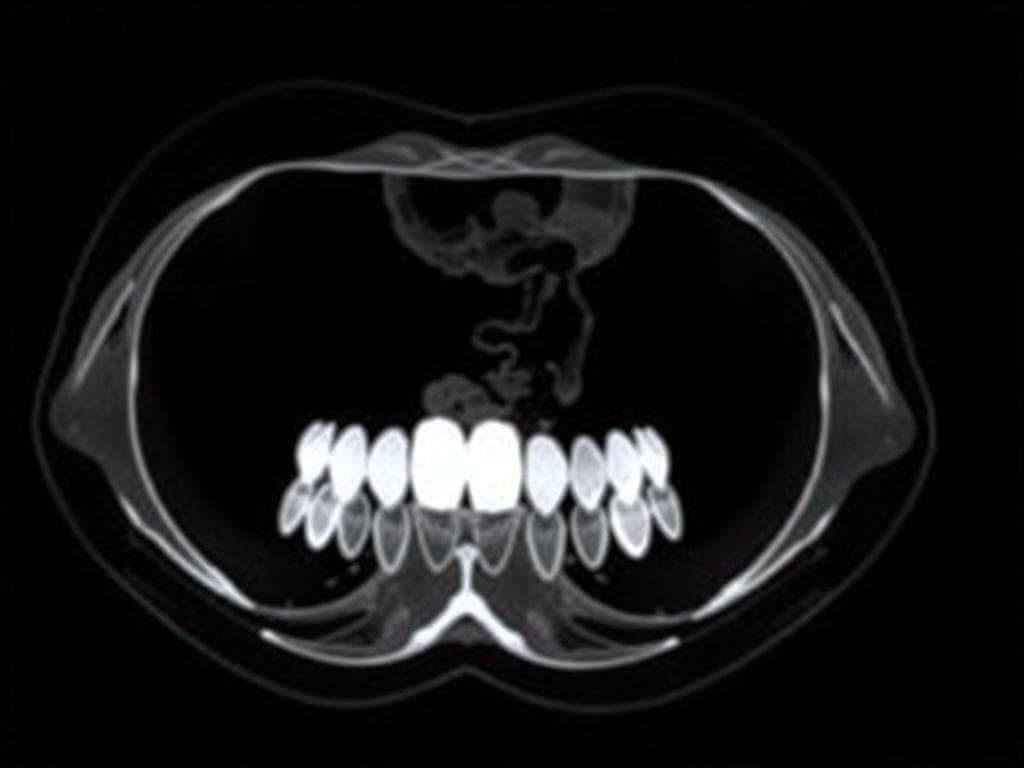

Термин «КТ зубов» обычно относится к конусно-лучевой компьютерной томографии, её ещё называют CBCT. Это метод, при котором специальная линейка датчиков и источник излучения вращаются вокруг головы и получают серию снимков, из которых компьютер собирает трёхмерную модель. Получается объёмный снимок челюстей, зубов и близлежащих структур.

Чего ждать от снимков: как врач использует данные

После съёмки врач получает набор послойных изображений и 3D-модель. Это позволяет измерить расстояния в миллиметрах, оценить плотность кости, увидеть расположение корней и близость нервных каналов. Для имплантации это незаменимо: планируя имплант, доктор точно видит, где пролегает нижнечелюстной нерв и может выбрать оптимальную длину и диаметр импланта.

В эндодонтии томография помогает найти дополнительные корневые каналы и оценить степень распространения воспаления за корнем. В хирургии по КТ легче рассчитать траекторию удаления ретинированного зуба, минимизируя риск повреждения соседних структур.